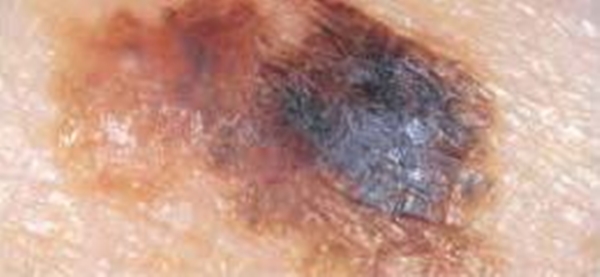

"Benin rengi homojense yani sadece tek renk hakimiyeti varsa sorun olmayabilir ama kahverengi, siyah, kırmızı gibi birden fazla renk oluşmaya başlamışsa büyüklüğü de 6 milimetrenin üzerindeyse tümör gelişimi açısından riskli benler olarak düşünülmelidir"

Peki kanser belirtisi olan benler nasıldır? Şekilleri ne tarzdır ve renkleri nedir? İşte şekil ve renkleriyle tehlikeli olabilecek ben örnekleri...

Ortası siyah kenarları kırmızı ben